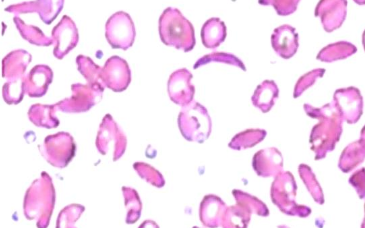

This is the peripheral smear of a 14 year old patient who gets frequently admitted to the hospital due to bone and joint pain

Q1: Describe the abnormal findings in this smear? Sickle cells.

Q2: what’s your diagnosis? Sickle cell anemia.

Q3: Name any type of crisis which can occur in this disease? Aplastic crisis, acute chest syndrome.

Q4: What are the ttt options for this disease? Hydroxyurea, blood transfusion, folic acid (not sure).